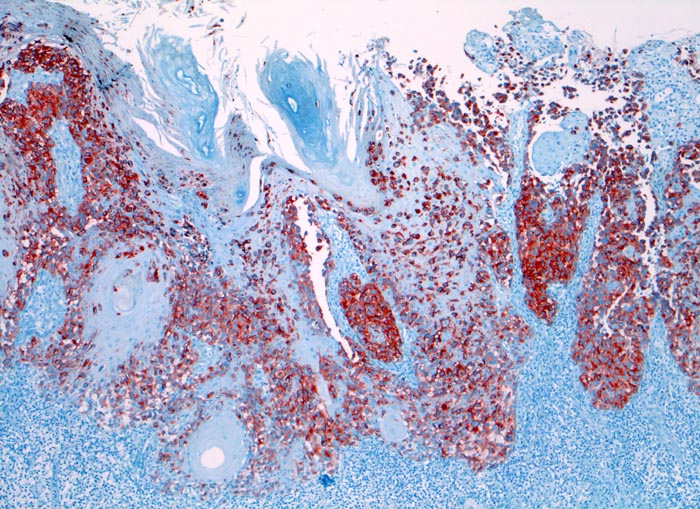

HMB-45

Anfärbung:

Zytoplasma

Reaktion im Normalgewebe:

Aktivierte Melanozyten und Naevi, Mammaepithel und Schweissdrüsenepithel.

Reaktion in Neoplasien:

HMB-45 wird in diversen melanozytären und nicht melanozytären Tumoren exprimiert:

• Naevi (meist nur oberflächlich)

• Malignes Melanom (90% Primärtumoren, 80% Rezidive und Metastasen, desmoplastische Variante meist negativ)

• Angiomyolipom

• Lymphangioleiomyomatose

• Klarzelltumor der Lunge (Sugar tumor)

• Einzelne Mammakarzinome, Speicheldrüsentumoren, Karzinome, multiple Myelome

Diagnostischer Nutzen:

Identifikation der verschiedenen HMB-45 positiven Tumoren.

Spezifität für maligne Melanome höher als S-100, aber niedrigere Sensitivität.